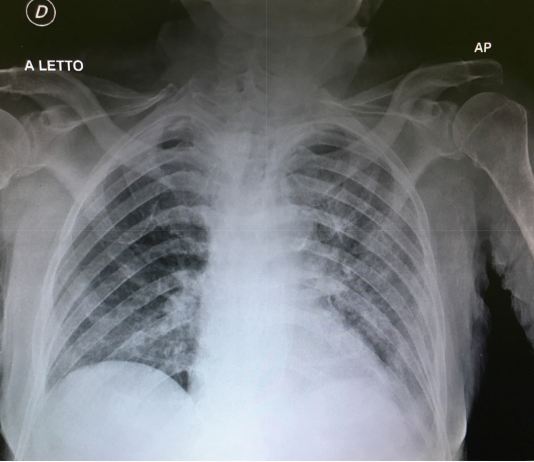

Maschio, 45 anni.Esegue come paziente ambulatoriale RX torace standard in due proiezioni:

plurimi addensamenti parenchimali peribroncovasali in sede perilare polmonare destra, nel campo polmonare...